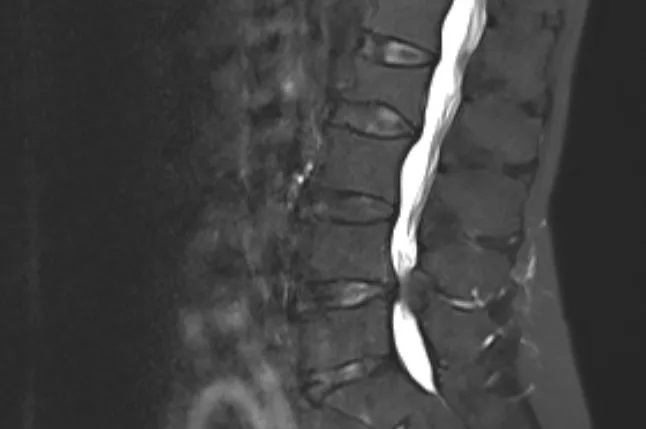

多年来,她一直被腰背部及左下肢的反复困痛、麻木所困扰,在多家医疗机构就诊后,被诊断为“腰椎椎管狭窄症”。

简单来说就是腰椎的神经通道(椎管)变窄了,从而压迫到内部的脊髓或神经根,引发腰腿疼痛、麻木、无力等一系列症状。

椎管狭窄:则是 “骨性结构或韧带增厚” 挤压了神经通道。

因其长期承受应力而劳损,会发生弹性下降、增生肥厚甚至钙化。肥厚的黄韧带从椎管的后方和侧后方凸入椎管,直接减少椎管的有效空间,压迫神经。

椎间盘的退变、脱水,导致的椎间盘的突出或者膨出。突出或者膨出的椎间盘从椎管的前方卡压神经。

关节突关节的肥大增生,从后外侧卡压神经。